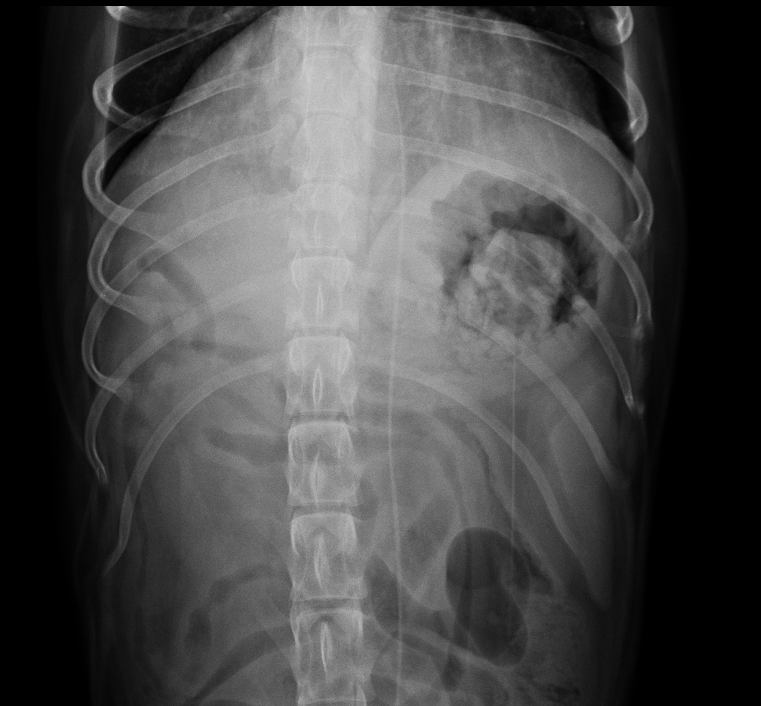

胃食道異物夾取手術精選輯 圖多慎入 首頁 病例分享 內視鏡微創治療 胃食道異物夾取手術精選輯 圖多慎入 傳統食道異物、胃異物都必須手術切開身體後把異物取出,可能會有手術的併發症、術後疼痛、需要住院、傷口照護的問題。 使用無創內視鏡 直接夾取異物,身體沒有任何創口、術後沒有傷口需要照護、也沒有手術造成疼痛感,也可以避免需要居家照護傷口的麻煩事。 **但有些狀況仍必須傳統切開手術喔** 本院隨機分享異物病例及吃進去的東西 襪子 ---- 髮圈 ---- 小豬玩具 ---- 雞骨頭 ----